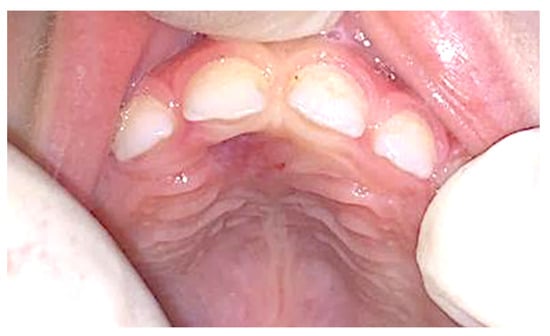

2. Case Presentation

| 19 | This study (2023) | Male/4 years | Maxilla, palatal region | Peripheral ossifying fibroma | Peripheral developing odontoma | Surgical laser excision |